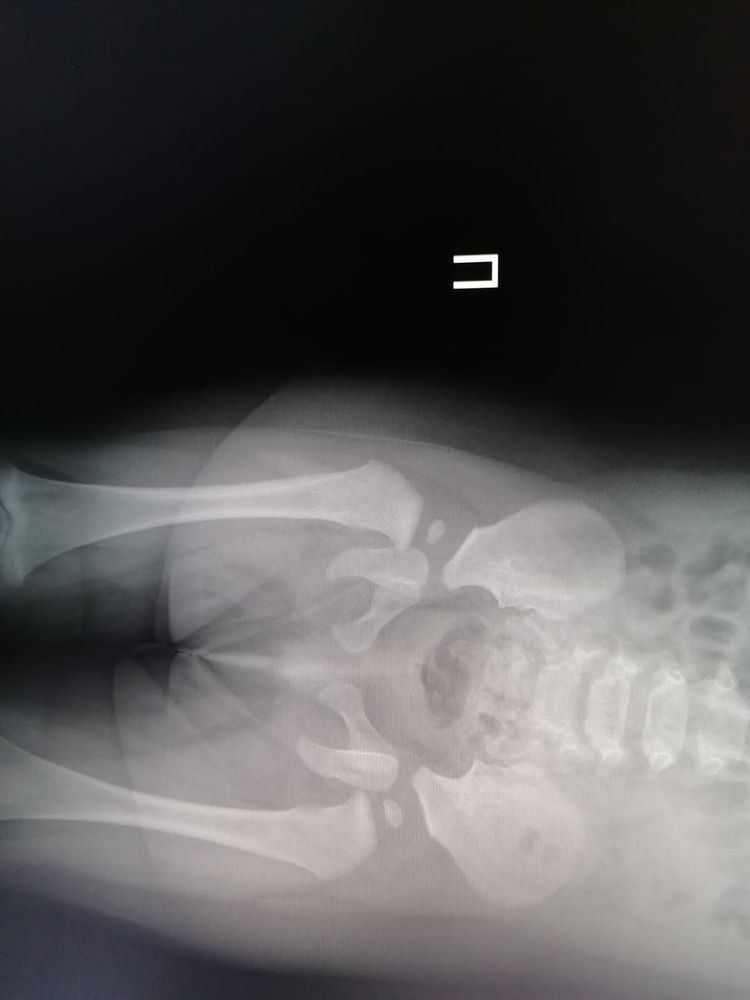

Малышке 7,5 месяцев, прошли второй курс массажа и на массаже мне сказали,что надо сходить к ортопеду,массажистке не понравилась правая ножка у малышки. Мы пошли к ортопеду,он осмотрел визуально нас,сказал,я ничего не вижу,но сходите на рентген. Пошли га рентген и там описали снимок,дали заключение вывих правого тазобедренного сустава ножки под вопросом. Дали нам направление на осмотр в клинике ортопедии и травматологии в Москве. Сегодня поехали туда,там нас осмотрел ортопед и невролог. Ортопед сказал,что визуально складочки на ножках не равномерно и правая ножка короче левой на 0,5 см, посмотрела наш снимок рентгена и сказала,что по снимку нет дисплазии. Сказала,что это тонус такой,мышечная недостаточность так сказать,ничего страдного,сказала делать массажи,плаванье,парафин и электрофорез.

Вот прикрепиляю снимет рентгена и заключение ортопеда и невролога из Москвы на сегодняшнем осмотре. Я вот вроде немного успокоилась,врач сказал никаких шин и распорок в нашем случае не нужно. Разве из-за тонусу может быть ножка чуть короче другой и неравномерные складочки. Думаю что делать дальше,можно успокоится или еще раз сделать снимок. Может у кого-то была похожая ситуация